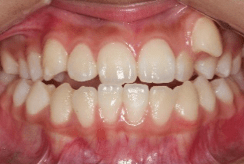

小児矯正で成長の誘導を行っても解決できない問題が残る場合は、永久歯が生えそろった後に改善が必要となります。永久歯が生えそろう中学生くらいから矯正治療をはじめることが多く、もちろん成人になっても矯正治療は可能です。ブラケットという固定式の矯正装置を使って歯をそれぞれ移動させ、きれいな歯ならびを完成させます。